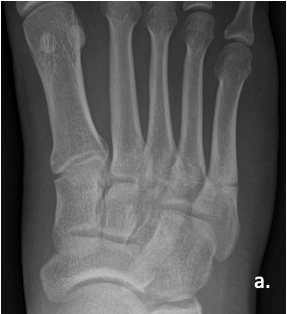

Figure 3a

Figure 3a. A 28-year-old Army officer injured during combatives was able to walk 2 days post-surgery. He started wearing his Army boots 2 weeks after surgery and completed Sapper School 10 weeks after surgery. He then went to Special Forces training within 6 months postop. The patient never had any pain after surgery. Here is the foot when the patient got injured.

Figure 3b

Figure 3b. A 28-year-old Army officer injured during combatives was able to walk 2 days post-surgery. He started wearing his Army boots 2 weeks after surgery and completed Sapper School 10 weeks after surgery. He then went to Special Forces training within 6 months postop. The patient never had any pain after surgery. Here is the foot when the patient got injured.